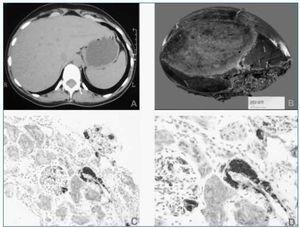

Las pruebas de imagen realizadas (ecografía y TAC abdominal) muestran una imagen de gran tamaño compatible con adenoma hepático en lóbulo hepático derecho (fig. 1a), con riñones de tamaño y ecoestructura normal. Se realiza seguidamente biopsia rectal que demuestra la existencia de depósitos de amiloide de tipo AA en los vasos de la submucosa (técnica de inmunohistoquimia).

Con el diagnóstico de síndrome Nefrótico secundario a amiloidosis en paciente con probable adenoma hepático, se remite al Servicio de Cirugía que programa su ingreso para intervención quirúrgica. En julio de 2003 se realiza hepatectomía parcial derecha (fig. 1b). El diagnóstico de adenoma hepático es confirmado histológicamente, observándose también depósitos de amiloide de tipo AA en el tejido renal, hepático y tumoral (figs. 1c, d).